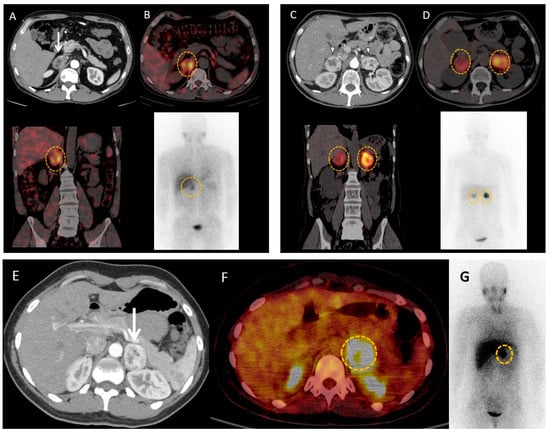

4.2. Contributions of Computed Tomography Using Dopamine and Glucose Analogues

4.3. Positron Emission Tomography with Computed Tomography Using Somatostatin Analogues

4.4. Current Guidelines for Molecular Imaging in Diagnosis and Staging of PPGLs